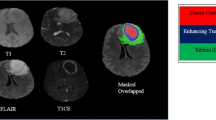

Graphical Abstract